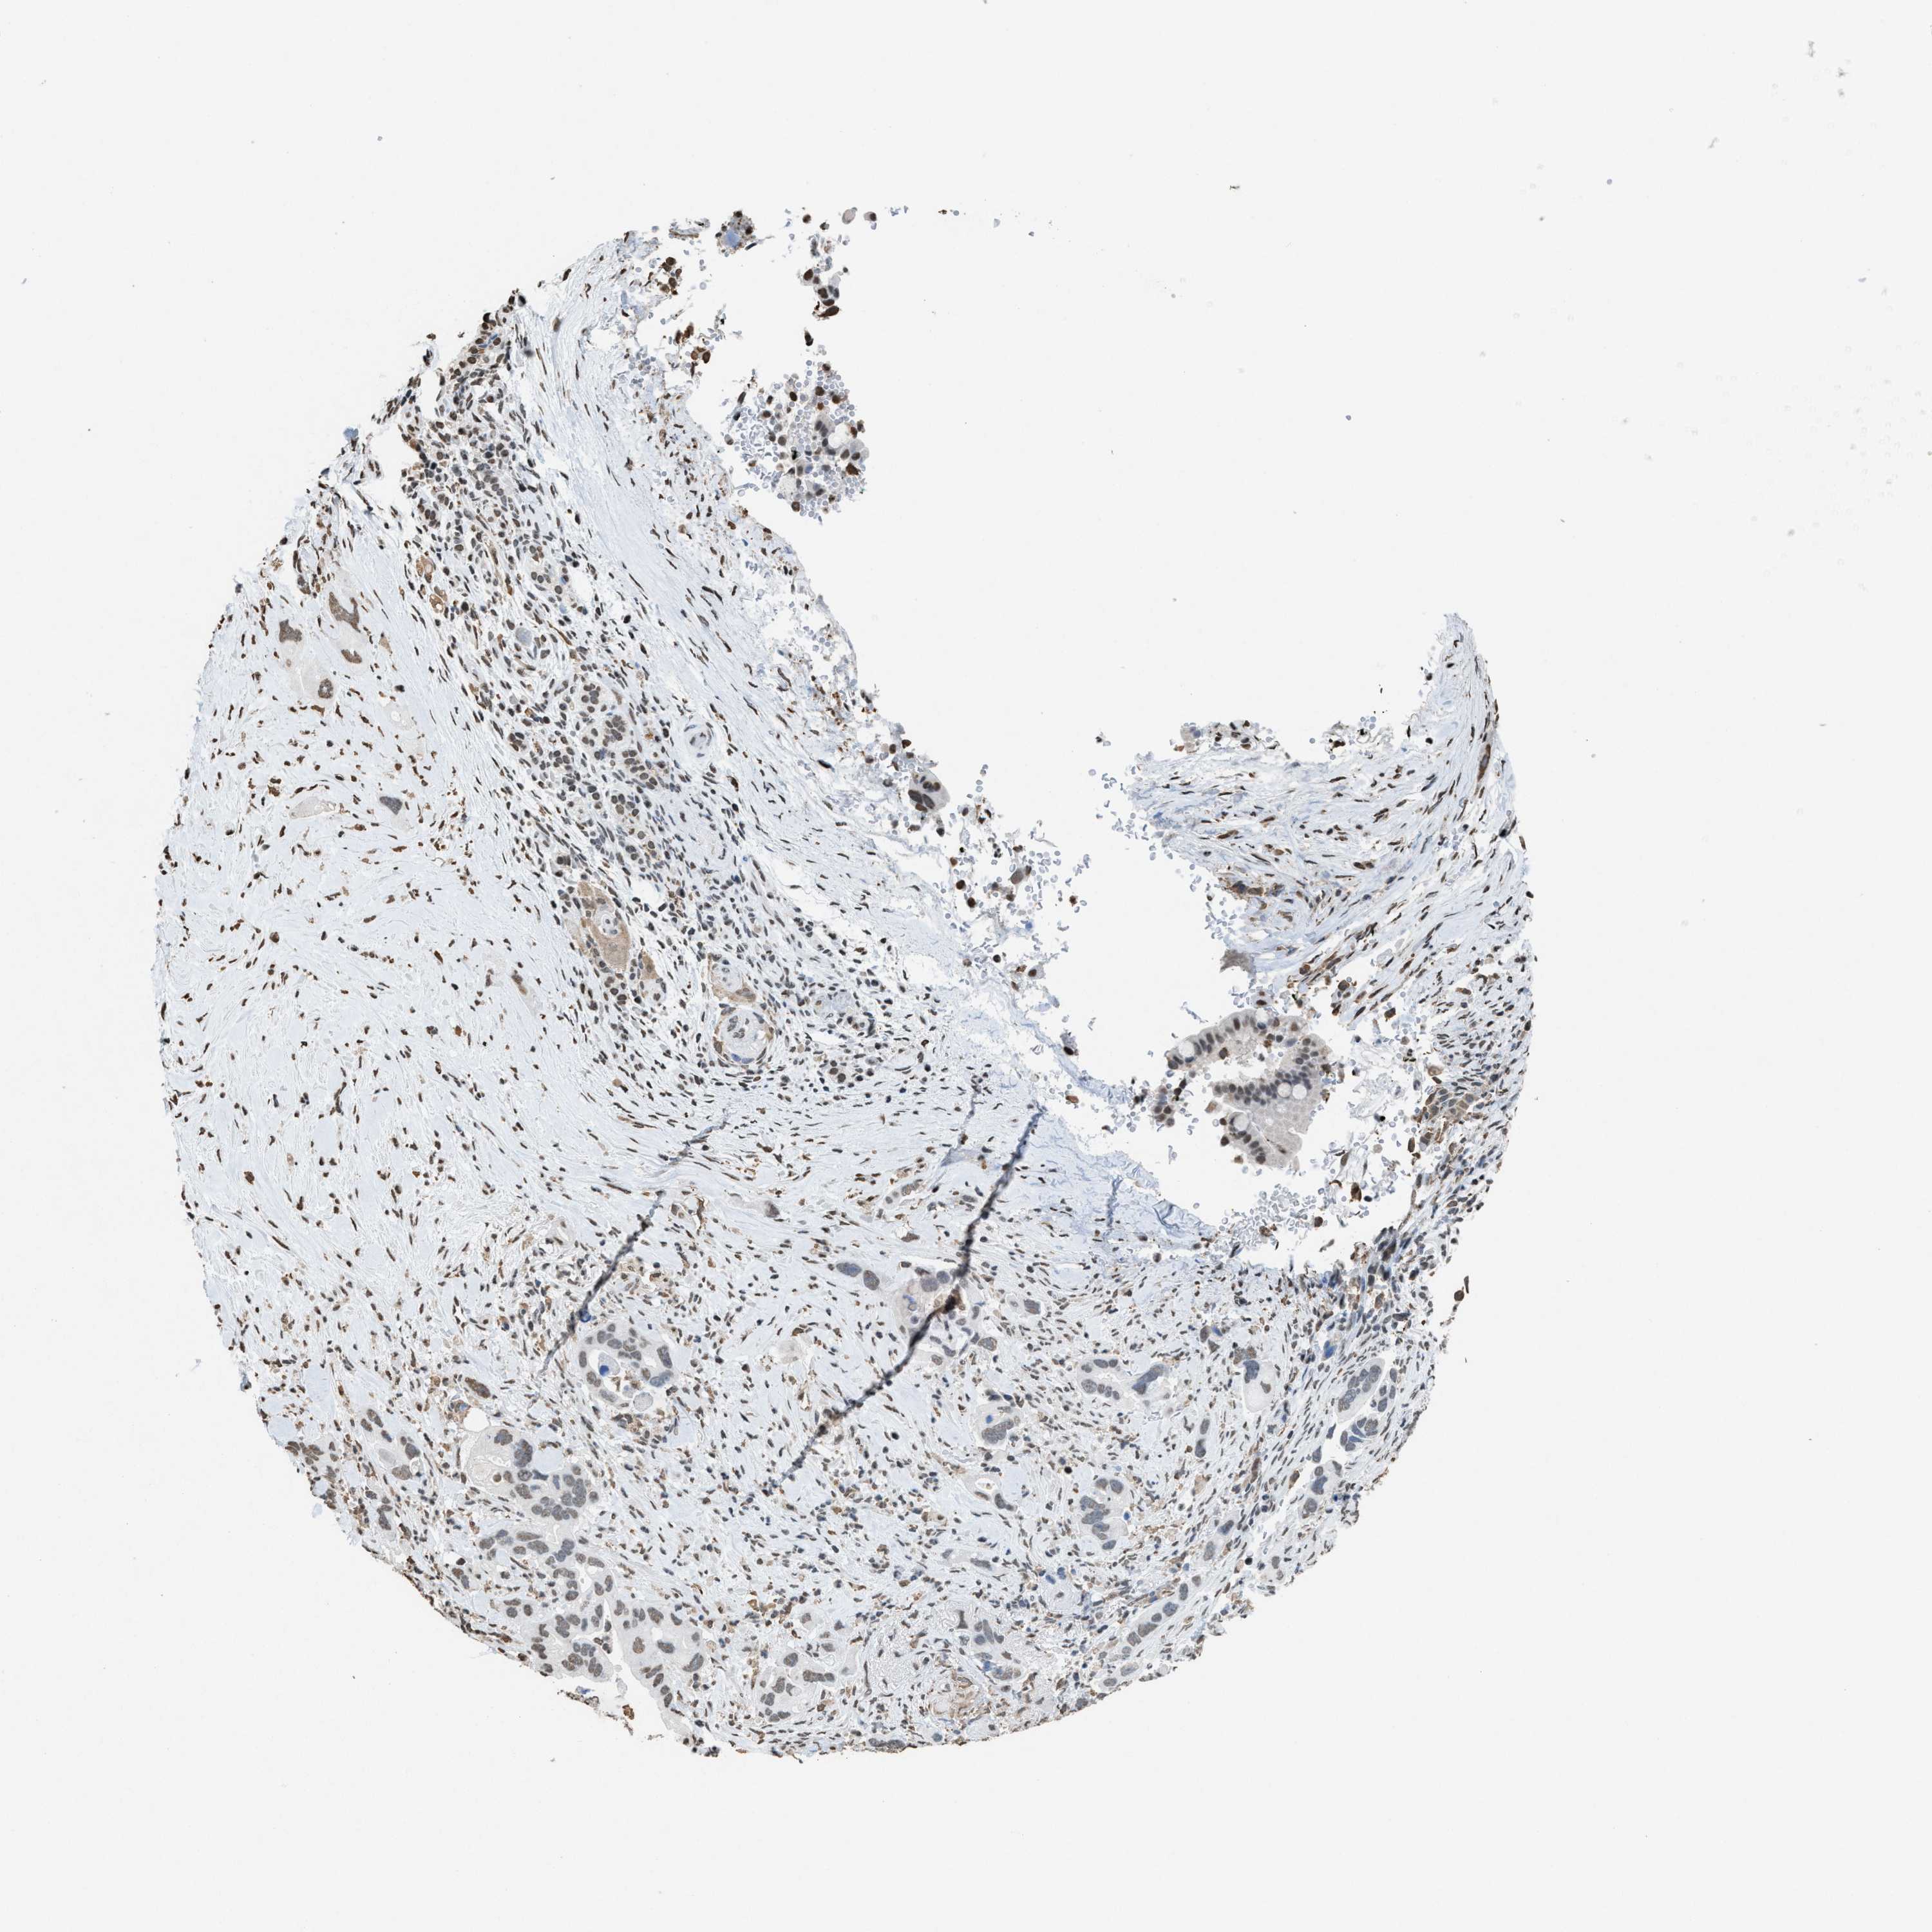

PANCREATIC CANCER - Protein expressioni

A mouse-over function shows sample information and annotation data. Click on an image to view it in a full screen mode. Samples can be filtered based on level of antibody staining by selecting one or several of the following categories: high, medium, low and not detected. The assay and annotation is described here.

Note that samples used for immunohistochemistry by the Human Protein Atlas do not correspond to samples in the TCGA dataset.

Antibody stainingi

Antibody staining in the annotated cell types in the current human tissue is reported as not detected, low, medium, or high, based on conventional immunohistochemistry profiling in selected tissues. This score is based on the combination of the staining intensity and fraction of stained cells.

Each image is clickable and will lead to virtual microscopy that enables deeper exploration of all samples and also displays staining intensity scores, fraction scores and subcellular localization as well as patient and tissue information for each sample.

Antibody HPA021816

Antibody CAB002209

Staining

High

Medium

Low

Not detected

Intensity

Strong

Moderate

Weak

Negative

Quantity

>75%

75%-25%

<25%

None

Location

Nuclear

Cytoplasmic/membranous

Cytoplasmic/membranous,nuclear

Adenocarcinoma, NOS

Adenocarcinoma, metastatic, NOS